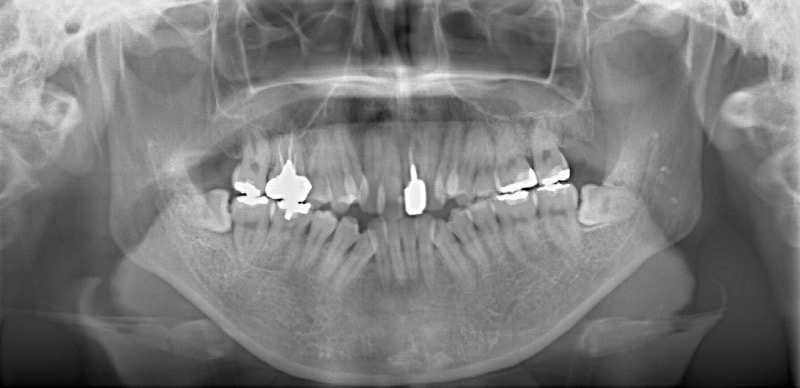

修復歯、補綴歯もあります。下顎8番が水平埋伏しています。

顎関節レントゲン分析

反対咬合の方はやはり下顎肢が細い傾向にあります。

歯根のパラレリング(平行性)が獲得されております。

下顎8番は、両側抜歯済みです。

顎位は良好な状態です。